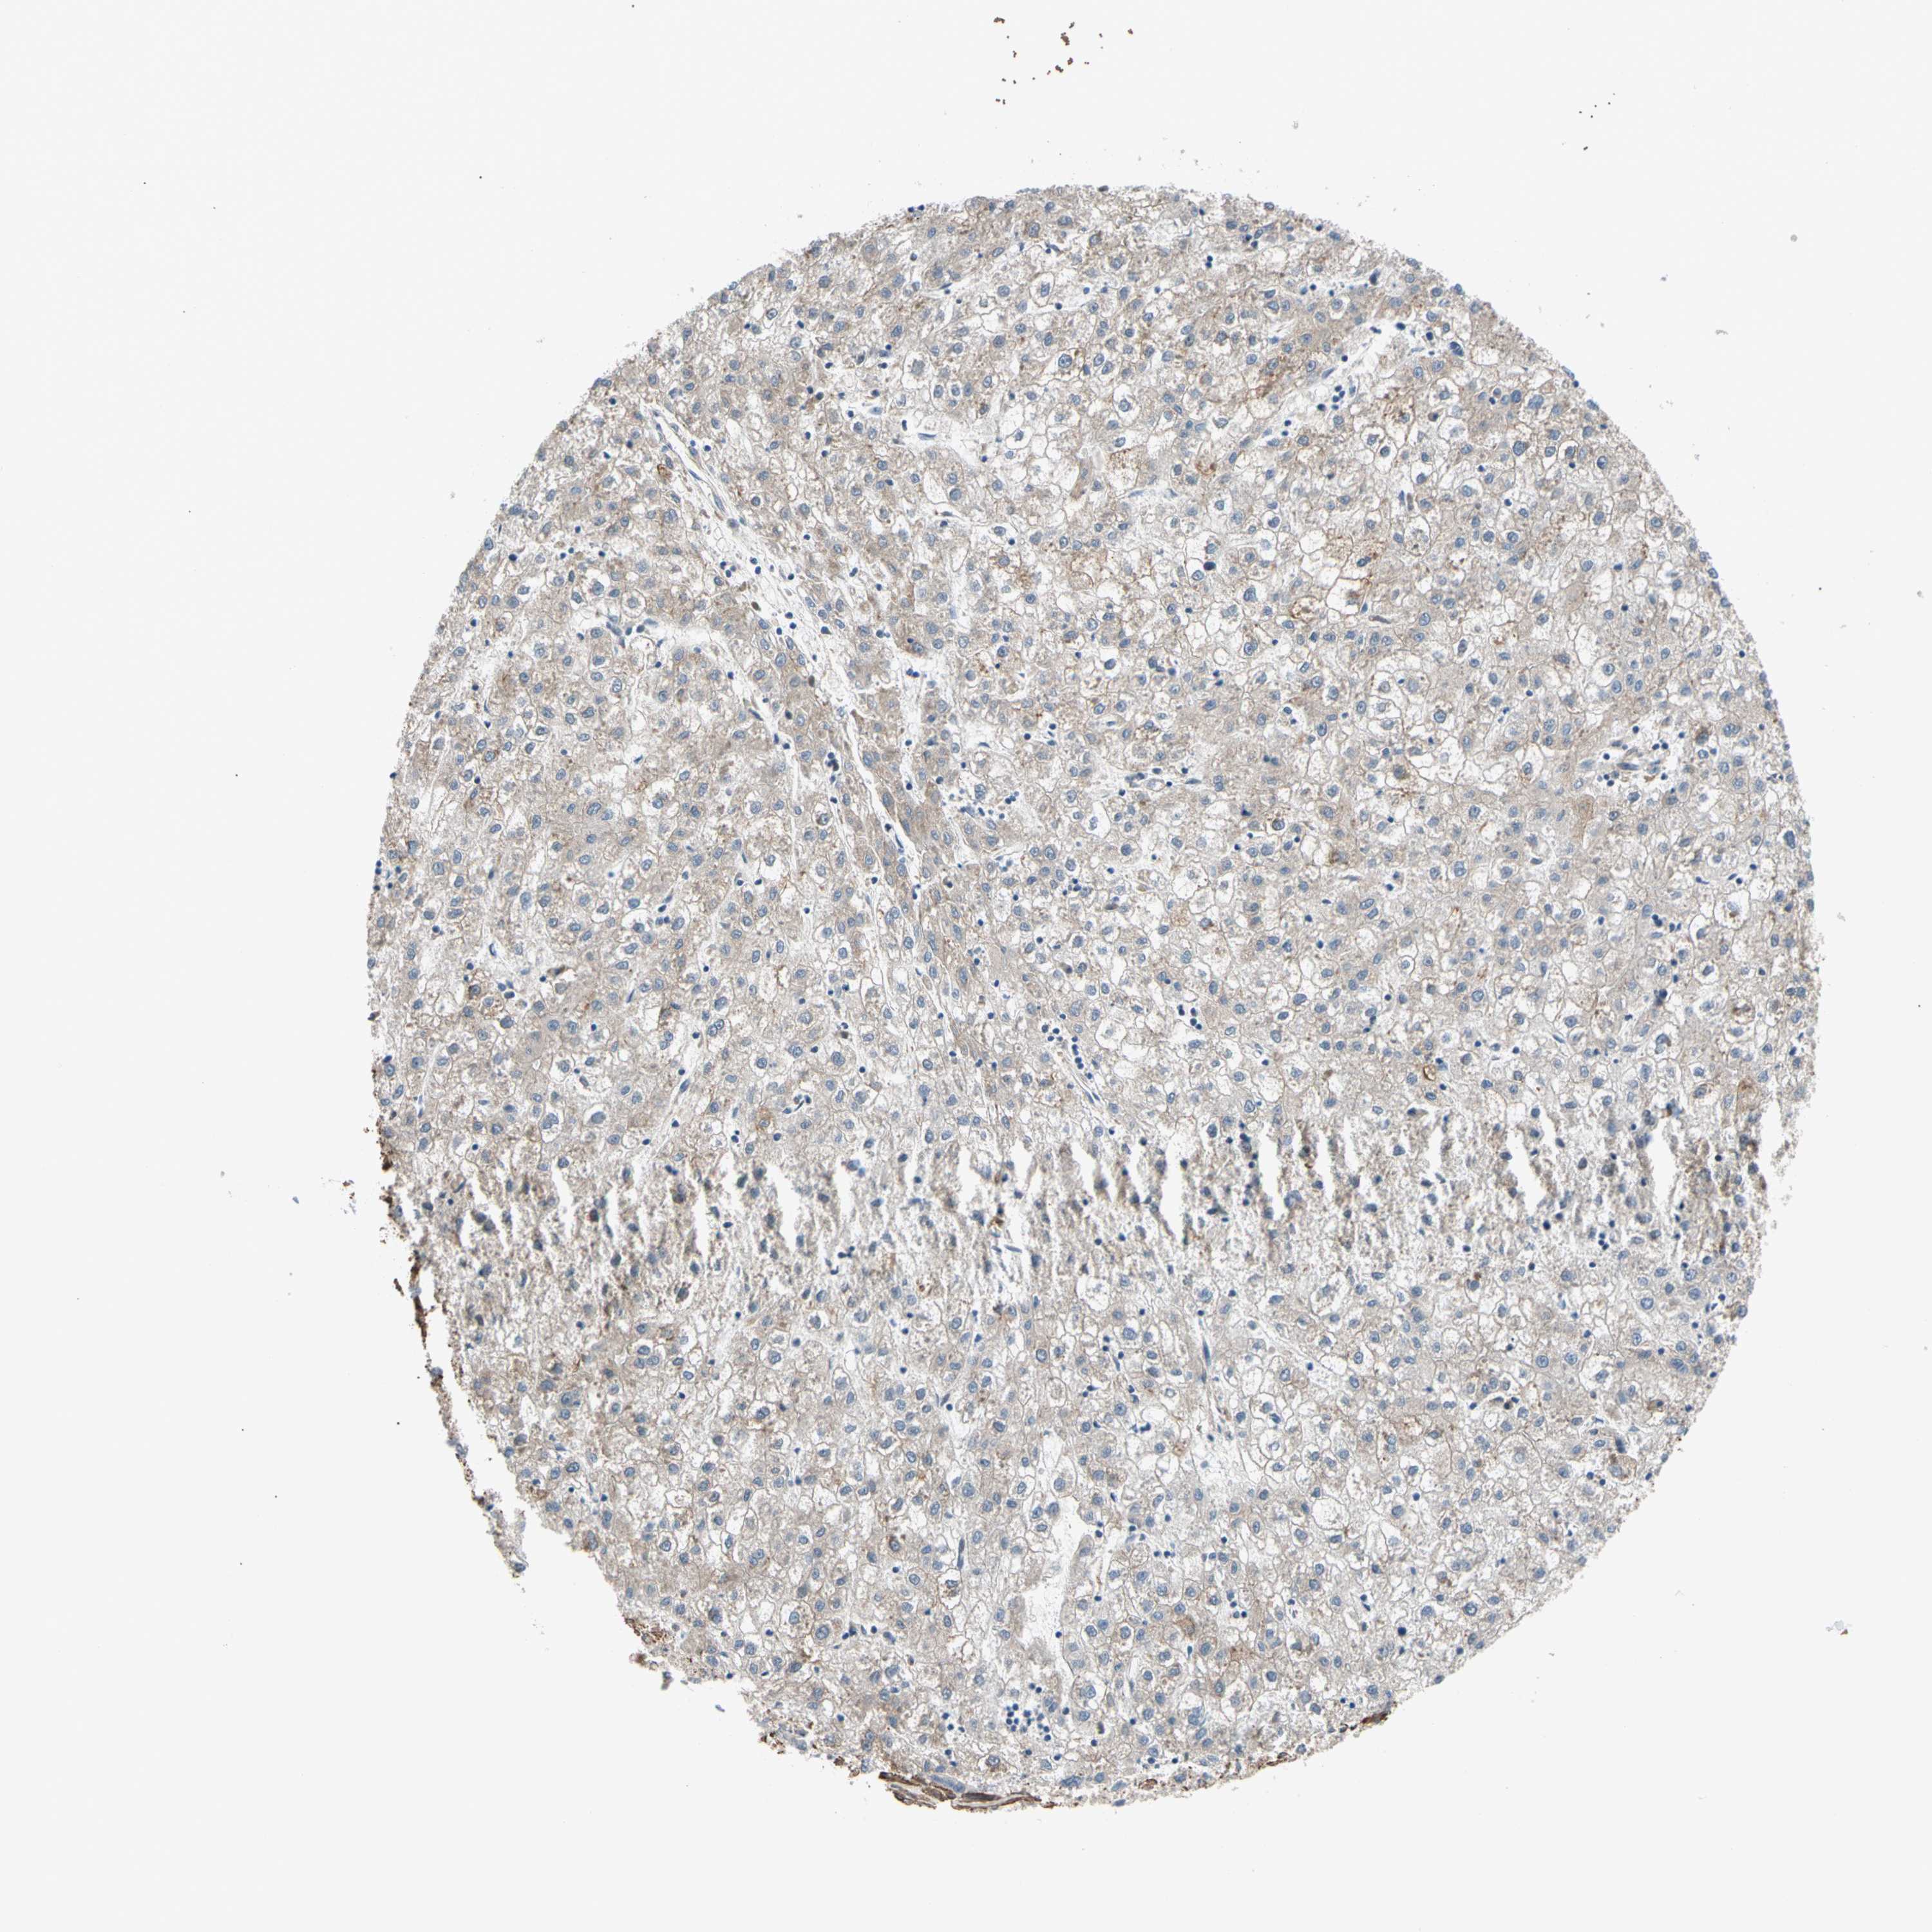

LIVER CANCER - Protein expressioni

A mouse-over function shows sample information and annotation data. Click on an image to view it in a full screen mode. Samples can be filtered based on level of antibody staining by selecting one or several of the following categories: high, medium, low and not detected. The assay and annotation is described here.

Note that samples used for immunohistochemistry by the Human Protein Atlas do not correspond to samples in the TCGA dataset.

Antibody stainingi

Antibody staining in the annotated cell types in the current human tissue is reported as not detected, low, medium, or high, based on conventional immunohistochemistry profiling in selected tissues. This score is based on the combination of the staining intensity and fraction of stained cells.

Each image is clickable and will lead to virtual microscopy that enables deeper exploration of all samples and also displays staining intensity scores, fraction scores and subcellular localization as well as patient and tissue information for each sample.

Antibody HPA008183

Antibody HPA053882

Antibody CAB019313

Staining

High

Medium

Low

Not detected

Intensity

Strong

Moderate

Weak

Negative

Quantity

>75%

75%-25%

<25%

None

Location

Nuclear

Cytoplasmic/membranous

Cytoplasmic/membranous,nuclear

Cholangiocarcinoma

Carcinoma, Hepatocellular, NOS